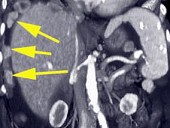

- 单项选择题女,55岁, 结合所示图像,最可能的诊断是 ( )

A、卵巢癌种植转移

B、间皮瘤

C、良性肿瘤

D、石棉沉积症

E、以上都不是